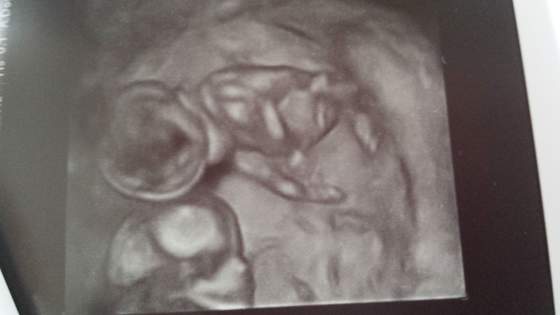

Aaa no i ja u swojego płaciłam 120 zł ale nie wiem czy to ze względu na to że jestem jego pacjentką, i nawet 3D dostałam :) 20140217_111021.jpg

• 20140217_111021.jpg

20140217_111021.jpg

12 KB · Wyświetleń: 91